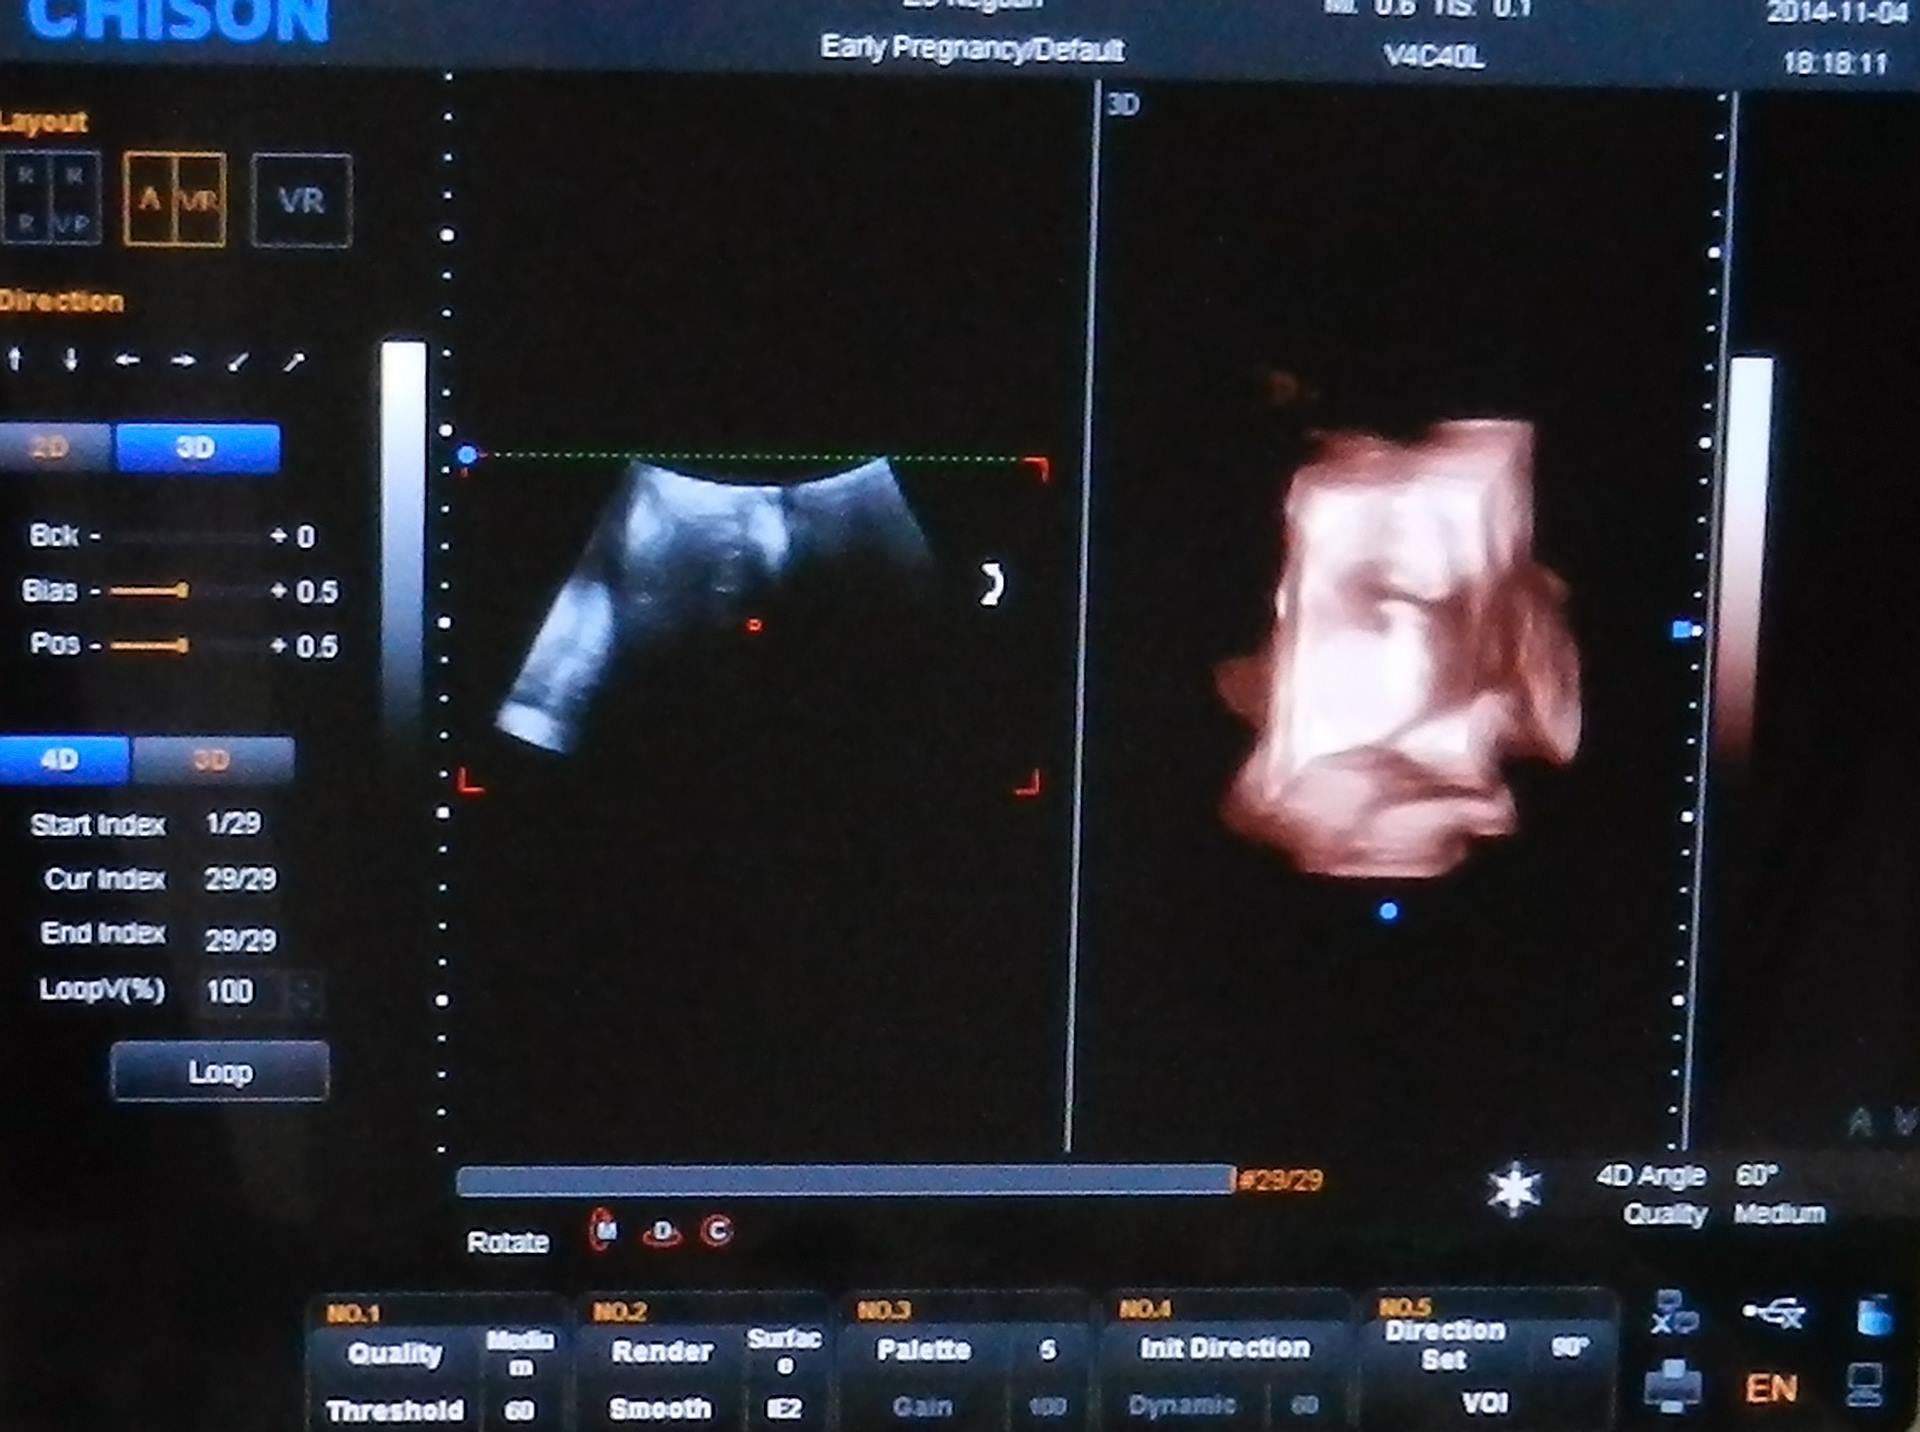

U poslednjem donatorskom paketu američke Vlade koji je stigao na adresu Zdravstvenog centra Negotin, nalaze se najsavremeniji 4 D ultrazvučni ginekološki aparat sa kolor doplerom i dve ginekološke sonde, 6 mobilnih aspiratora i tri savremena EKG aparata. "Oprema će podići nivo zdravstvene zaštite u negotinskom Zdravstvenom centru, prvenstveno na Odeljenju ginekologije i akušerstva, što nam je veoma važno s obzirom na mogućnost kontrole trudnoće žena i rasta beba, kao i svih ostalih problema koji mogu da se jave tokom trudnoće i porođaja. Zahvalni smo Vladi SAD i Ambasadi u Beogradu, jer je i ovog puta bilo sluha za naše potrebe kao i u više slučajeva do sada i što je u relativno kratkom roku, odreagovano na naše zahteve u vezi traženih medicinskih aparata", ističe za East Side portal, dr Tihomir Milovanović, direktor ZC Negotin.

"Odeljenje ginekologije i akušerstva je bogatije za aparate iz američke donacije koji predstavljaju novinu u negotinskom zdravstvu. Ultrazvučni aparat 4D je najsavremeniji uređaj iz oblasti ultrazvučne dijagnostike i njegova tehnološka rešenja omogućavaju najbolji kvalitet „običnog“ prikaza ploda u dve dimenzije. Ima vaginalnu i konveksnu sondu i kolor dopler. Namenjen je trudnicama koje održavaju trudnoću na našem odeljenju, ginekološkim pacijentkinjama koje pripremamo za operacije ili su na odeljenju zbog drugih indikacija, porodiljama i pacijentkinjama smeštenim kod nas po tipu dnevne bolnice. Siguran sam da ćemo, zahvaljujući ovom vrhunskom aparatu, raditi kvalitetniju dijagnostiku tumora i drugih procesa na genitalnim organima žena", ističe prim. dr Siniša Čelojević, specijalista ginekologije i akušerstva, načelnik istoimenog odeljenja, na kome je od početka godine do sredine novembra rođeno samo 170 beba. Deleći nadu svih zaposlenih da će Krajinke češće rađati, zaposleni u ZC Negotin su najavili da bi do kraja godine trebalo da stigne oprema iz još nekih donacija koja će doprineti podizanju kvaliteta pružanja zdravstvenih usluga svim pacijentima.